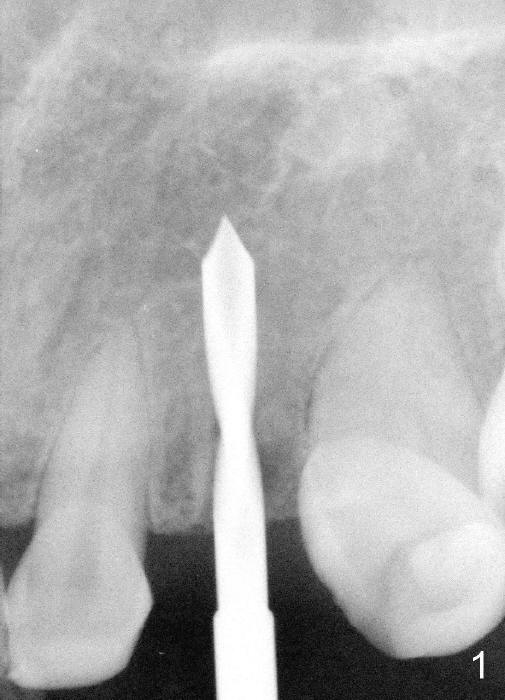

The 42-year-old lady refuses to take antibiotic prior to surgery due to lactation. The extraction of the upper left deciduous canine is not difficult as expected. There appears to be no granulation tissue. What is unexpected is difficulty in osteotomy. Initial osteotomy is too palatal, apparently perforating the palatal plate. The osteotomy has to be changed: slightly palatal to the center of the original socket (Fig.1: 2 mm pilot drill). As drills increase in diameter, the coronal end of the drills have to be tilted buccally, because it feels like that the labial plate at the apical end is going to be perforated. When 4.5x14 mm bone level implant is placed, the implant is sticking out too much (Fig.2). To alleviate this cosmetic issue, the implant is placed deeper (Fig.3). A 25º angled abutment is placed with heavy labial reduction (Fig.4,5). The patient is pleased with a stable new tooth, but the operator is not (Fig.6). Removal of the implant may be not the wildest guess. Two or three days postop, the patient reports pain and swelling. The symptoms disappears after antibiotic. One week follow up reveals wound healing normal. The gingiva returns to its normal color, as compared to purplish appearance in Fig.4,6 (immediately postop). In fact, the implant fails in a month.